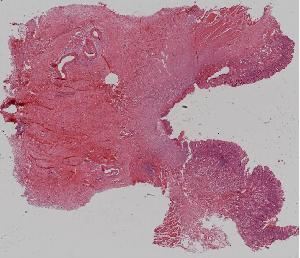

47.心肌梗死